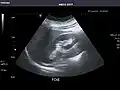

Renal ultrasonography

Ultrasonography of the kidneys is essential in the diagnosis and management of kidney-related diseases. The kidneys are easily examined, and most pathological changes in the kidneys are distinguishable with ultrasound.[7]